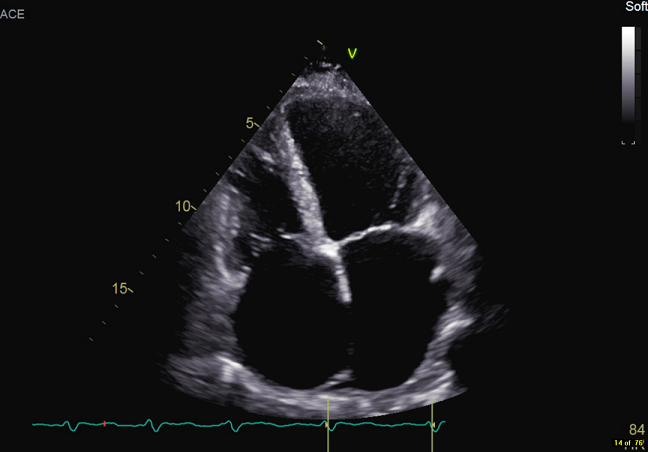

经过一段时间的对症治疗,患者症状有所缓解,但复查结果显示二尖瓣及三尖瓣仍为重度关闭不全,经心外科团队共同探讨,患者具备外科手术指征,决定在全麻体外循环下行二尖瓣置换术、三尖瓣成形术、左心耳缝合术 。术后患者恢复良好,现已治愈出院。

术后彩超影像